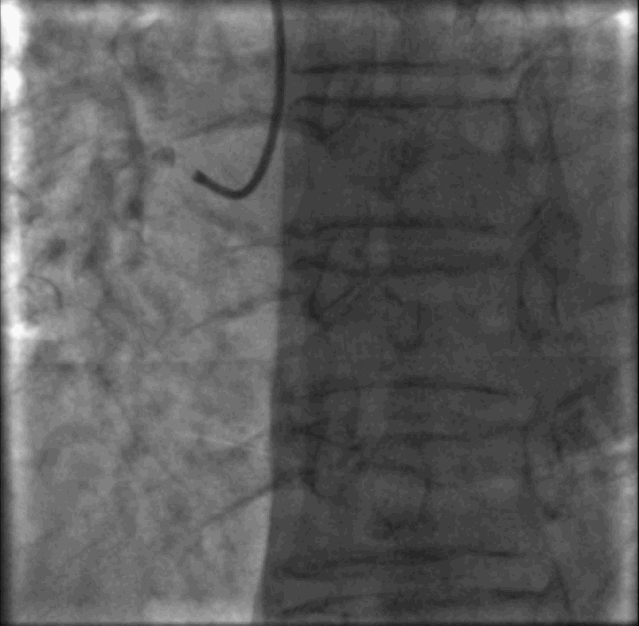

介入治疗——预处理2

2.5-13mm棘突球囊以8-10ATM扩张RCA-PLA靶病变, 狭窄进一步减轻,未见夹层。